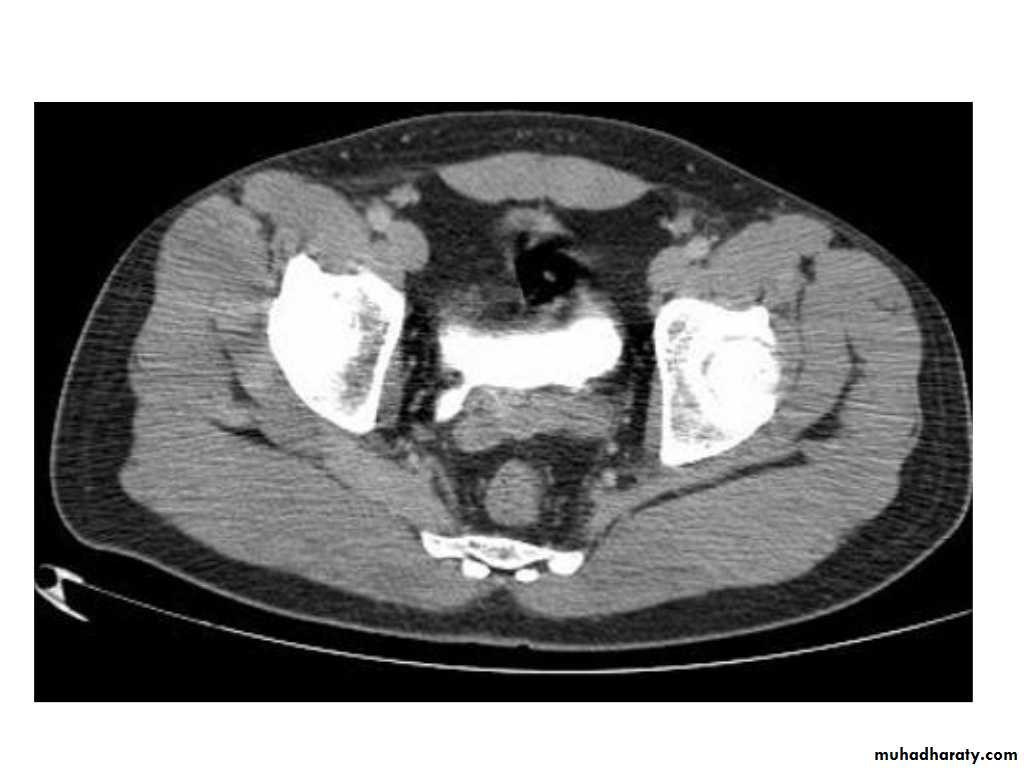

IVU shows

1. The kidneys at low position .2.Close to the spine with long axis parallel to the spine

3. Malrotation manifested by medially directed calyces.

4- The renal pelvis and ureters are anterior and lateral in position.

5- Hydronephrosis and calculi highly associated.